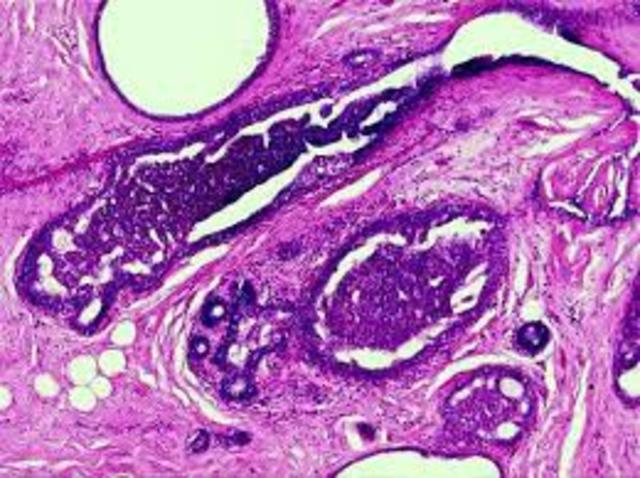

• CRECIMIENTO Y DESARROLLO

CRECIMIENTO Y DESARROLLO

Se produce el verdadero crecimiento y desarrollo de la telemedicina, con el florecimiento de las redes de telecomunicaciones y de internet, y con la aparición de

las principales aplicaciones de la telemedicina (telerradiología, telepatología, teledermatología).

Esta década supone la gran proliferación de experimentos de telemedicina, muchos de ellos con un objetivo de continuidad y rentabilidad.